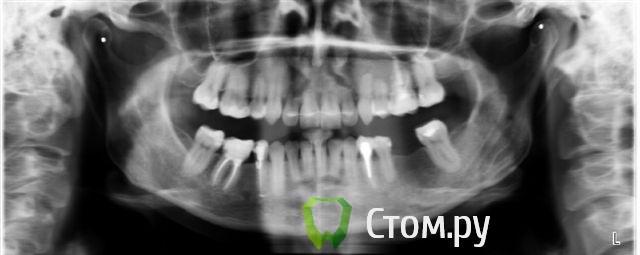

Александрстрад Опубликовано 8 ноября, 2011 Поделиться Опубликовано 8 ноября, 2011 Уважаемые доктора! Потерял и веру и надежду в возможность решения проблемы у своей жены. Одел на нее брекеты у знакомых ортодонтов в Москве, результаты, которых видел. В процессе лечения консультировался и ЦНИИСЕ у Арсениной и у других докторов, работал в крупнейшей медицинской компании, доступ к врачебной базе был очень большой. В процессе лечения все говорили что лечение идет нормально, а когда сняли брекеты ужаснулись все. Хронология лечения у ортодонта описана ниже, включая проблемы, которые мы получили после лечения.1. Показания к лечению брекет-системамиХруст при жевании в правом суставе.Замещение отсутствующего на нижней челюсти пятого зуба справа в течение 10 лет. В результате отсутствия 5-го зуба: наклон 4-го и 6-го по направлению друг к другу, резорбция (убыль) костной ткани на челюсти на месте отсутствующего зуба.Левый клык на верхней челюсти выходил из зубного ряда.Смешение центра верхней челюсти влево.Правый клык до момента начала лечения на верхней челюсти не вышел, находился в состоянии ретинированного, т.е. не вышел.2. Этапы леченияНачало лечения брекет системой - 2006 год.Снятие брекет системы 2009 год.Что было сделано:1. Левый клык на верхней челюсти был поставлен в зубной ряд.2. По отсутствующему 5-му зубу на нижней челюсти - доктор принял решение по замещению, путем передвижения зубов на нижней челюсти вправо,что и было проделано.3. Через 2 года ношения брекет-системы было принято решение по вытаскиванию левого ретинированного клыка.Был удален 3-ий зуб и в освободившееся пространство был вытянут клык.В результате данного объема работ и некорректной работы доктора,были завалены внутрь зубы на верхней челюсти - левая сторона, начиная от 1-го и далее, от резцов до жевательных.Также после сделанного панорамного снимка выяснилось, что произошло рассасывание корней 4-х фронтальных зубов на верхней челюсти более 65%.4. Также в процессе лечения был потерян 6-ой зуб на нижней челюсти слева. Проблемы сейчас1. Хруст в челюсти при жевании и зевании не прекратился, а появился и слева.2. Заваленная левая часть зубов на верхней челюсти не позволяет смещать нижнюю челюсть влево,тем самым перегружаются жевательные мышцы справа, в результате бывают головные боли и боли в мышце при жевании.3. Рассасывание 4-х верхних зубов.4. Расстояние справа между верхней и нижней челюстью на данные момент 3 мм. Сделали после снятия бректов исселдование у ортопеда, заключение ниже. Ее приговор - ТОТАЛЬНОЕ протезирование.Жене 36 лет, она даже слышать об этом не хочет. ПОМОГИТЕ РЕШИТЬ ПРОБЛЕМУ, НАДЕЖДЫ БОЛЬШЕ НЕТ. Заключение ОРТОПЕДАTreatment objectives∙ Transversal and sagittal discrepancy- make passive centic arch of upper jaw fit to active centric active lower jaw∙ First interference contact in RP on 24-34 and 37-27 with disocclusion for + 2 mm. Rp= 0=-2 mm, and till last contact =-4mm on incisal pin, so increase IP for =+3mm∙ Muscle problems∙ Change OPI on right side from 15 degrees to 20 degreees and change Cui right side to∙ Increse LFH +3 mm on incisal pin∙ Curve of Spee will be accentuated for 36∙ Steep condyle- decreased radius curve of Spee∙ Cui for 13 is not more than 55 degrees∙ Curve of Spee=Curve of wilson for 36 and 46∙ Rotation of mesial cusp of 6 down- change OPI for 36 – rotate 36 with mesial contact point OPI 6 = 35 degrees for DOA=12 degrees Ссылка на комментарий

Александрстрад Опубликовано 10 ноября, 2011 Автор Поделиться Опубликовано 10 ноября, 2011 А эти ТРГ на каком этапе делались (боковая и прямая)? По описанию МРТ я так и не понял, смещение диска вправляемое или нет, словосочетание "полная репозиция" для меня не совсем привычное? Решение ортопеда с тотальным протезированием тоже требует дополнительных комментариев от него, каковы этапы подготовки к такому протезированию, да вообще, необходимо выяснить, есть ли достаточный опыт ведения пациентов с дисфункцией ВНЧС? В любом случае, первый этап - лечение и стабилизация ВНЧС, но одним только балансом положения нижней челюсти результат врядли будет достигнут, необходимо работать с черепом и постурой, т.к. истинные проблемы с ВНЧС прибывают именно отсюда. 1. Снимок был сделан 2 недели назад.Дать комментарии по описанию снимков, к сожалению не могу. 2. По комментариям ортопедаВ рамках диагностики подготовлена презентация, где есть все снимки, слепки, графики.Если будет возможность ее просмотреть, буду благодарен.Готов отправить на электронную почту.Для жены данный вариант - это катастрофа. 3. По опыту врача.Врач был рекомендован по направлениям – ортопедия и гнотология, г-ном Чикуновым.Обучался врач и в России и в Австрии. Часть спорных работ отвозится в австрию.По стажу, примерно 5-7 лет практики.ФИО - Дзалаева Ф. К.По опыту работы с суставами – к сожалению, нет информации. Но есть вводная о том, что много работ корректировалось и исправлялось, после ортодонтического лечения, включая суставные. Если есть возможность рекомендовать доктора, который смог бы помочь в челюстной проблеме, был бы очень благодарен.Все возможные "ниточки" на врачей использовал. 4. Еще 3 вопроса – Сняли ретрейнер с нижней челюсти.На нижней челюсти был прикреплен фиксирующий ретрейнер, в течение 1,5 лет. После снятия брекетов, жена жаловалась на постоянный дискомфорт от его ношения (дикция), а также в ожидании того, что нижние зубы, которые передвинули вправо, чтобы заместить дефект отсутствующего 5-го зуба, как выяснилось потом, что этого делать не нужно было, из наклоненнего состояния вернутся частично в исходное состояние. Насколько было правильно решение, доктор, который снимал ретрейнер, сказал, что 1,5 года достаточно, я же читал, что период ношения ретрейнера в два раза больше периода ношения брекетов.Вопрос – необходимо наклеить заново ретрейнер, чтобы не прибавилось дополнительных проблем? И насколько есть вероятность того, что наклоненные зубы, хоть немного поднимутся вправо? - Замещение отсутствующего 6-го зуба на нижней челюсти.На нижней челюсти слева, потеряли зуб 1,5 года назад (киста, с воспалением). Насколько сейчас целесообразно заниматься имплантацией? Переживаю, что кость в челюсти будет «уходить» и потребуется костная пластика.А также на приеме у остеопата получил информацию, что 6-ой зуб, выполняет функцию «программного» для мозга, т.е. мозг дает правильную команду на смыкание челюстей при наличии 6-го зуба.Остеопат рекомендовал по возможности максимально оперативно установить имплант. - Перепрограммирование мышцТакже были на консультации у д-ра Ронкина, который рассказывал про возможность перепрограммирование челюстных мышц, за счет электороимпульсов, через датчики, прикрепленные на лице.Насколько это может помочь в нашей ситуации? Ссылка на комментарий